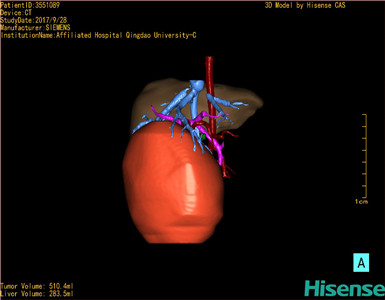

CT结果输入海信CAS系统后行3D重建及手术规划后,于2017-10-10全麻下行“肝肿瘤切除术”手术治疗:

术前三维重建及手术方案设计:

将0.625mm双源薄层CT资料的静脉期和动脉期Dicom格式文件导入海信CAS系统。

通过调节窗宽窗位调整CT序号,对肿瘤,肝实质,胆囊,下腔静脉,肿瘤,肝动脉、门静脉及肝静脉等进行三维重建;系统自动计算肿瘤体积和肝脏体积。

模拟手术操作,自动计算切除肿瘤体积。肝脏体积为453.7ml,通过比对2-3岁正常肝脏体积为475.97±99.7ml,通过术前模拟手术,精准判断切除后剩余肝脏体积能耐受,避免肝衰竭发生。

术前三维重建:

重建图片